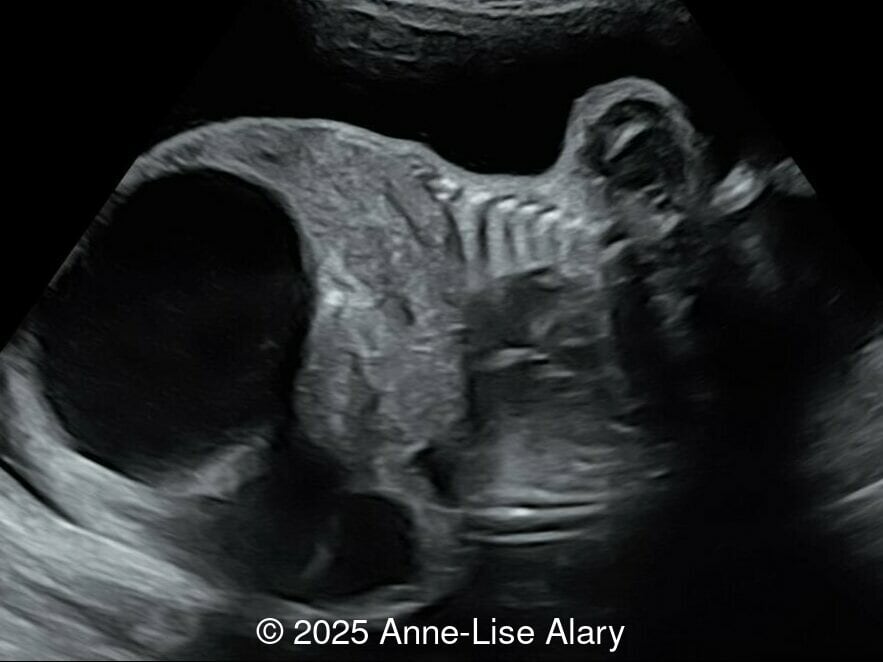

Our prenatal ultrasound revealed a male fetus with megabladder, dilation of both ureter and kidneys, and thinned kidney parenchyma consistent with Lower Urinary Tract Obstruction (LUTO). Additional findings suspected on ultrasound and confirmed on computed tomography included:

- Evidence of Potter's sequence due to the lower urinary tract obstruction with small thorax compared to the abdomen, hyperextended neck, and pes varus.

- Suspicion of dilated bowel in the left flank, in addition to dilated urinary tract

The diagnosis of PBS is often made in the second trimester of pregnancy, although it has been described as early as 11 weeks of gestation [20]. The most frequent ultrasound findings are a large, thin-walled bladder accompanied by bilateral hydroureter/hydronephrosis, dysplastic kidneys with echogenic renal parenchyma and renal cortical cysts, and abdominal wall laxity which is better viewed after bladder decompression [21]. Cryptorchidism can be detected prenatally by 28 to 30 weeks gestation when the testes descend into scrotum. There may be a patent urachus, visible as a cystic connection between bladder and umbilicus. Oligohydramnios is a frequent finding, which makes it difficult to visualize the associated anomalies.